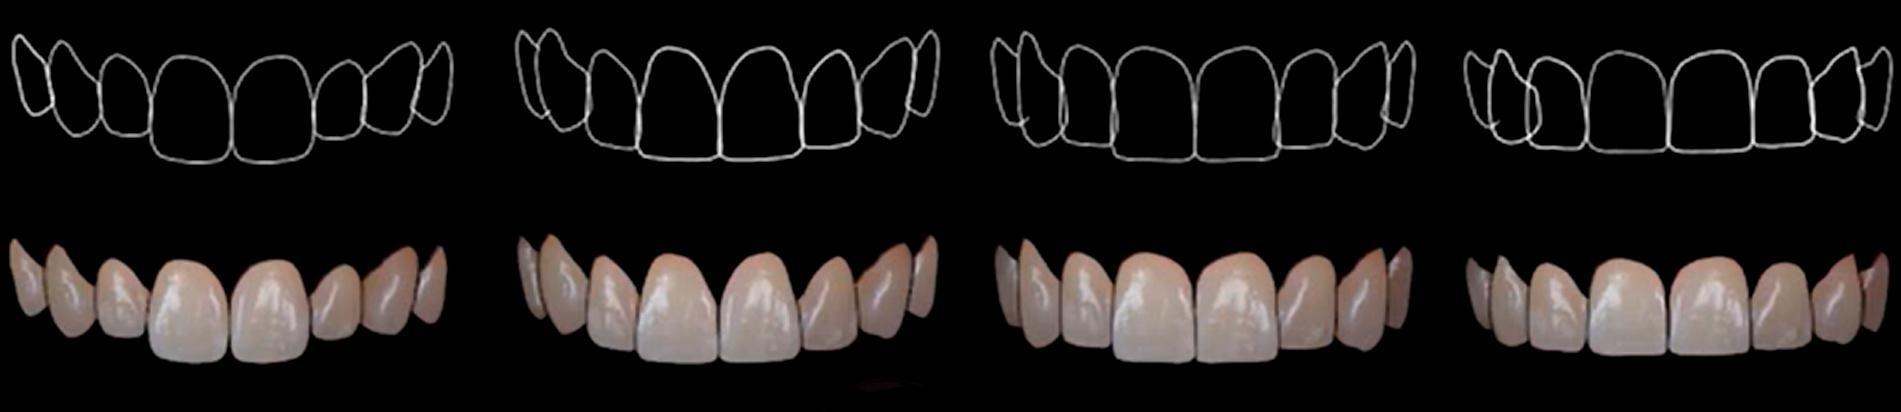

IMPORTANT! Let’s digress to remind you about gingival phenotypes. These are innate characteristics of the body that even correlate with a person’s appearance.

Common tooth shape variations associated with different amounts of keratinized attached gingiva: an elongated shape with high zeniths is most often associated with a thin layer of attached gingiva, while a square profile is associated with a thick phenotype. YouTube/ Implantarium/ Rauf Aliyev

If a person has a thin and graceful build, he will most likely have elongated teeth and the so-called thin-scalloped phenotype. This phenotype is characterized by long papillae and a relatively thin layer of attached gingiva. Conversely, if a person naturally has broad shoulders, thick hands, and a strong jaw, the gingival contour will likely be smoother, the teeth will appear square, and the attached gingiva will be thick and wide. The second type tolerates implant placement much better, and the complication rate is much lower.